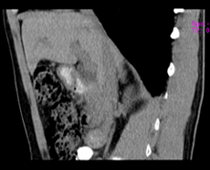

患者,男,57,常年不吃午饭,近一个月来腹部隐痛,无明显黄疸,明天进行增强扫描,图象另上传,麻烦各位帮忙一起看看讨论讨论

肝外胆管扩张,胰头增大,肠系膜上静脉似有包埋征象。

考虑:胰头占位性病变,建议增强进一步检查。

肝外胆管扩张,胰头增大,占位性病变可能性大.

胰头增大,考虑胰头占位性病变。

胰头增大,胆总管增宽,考虑胰头癌可能性大,明天看增强片有助诊断.

单纯性胆总管扩张,下端梗阻.